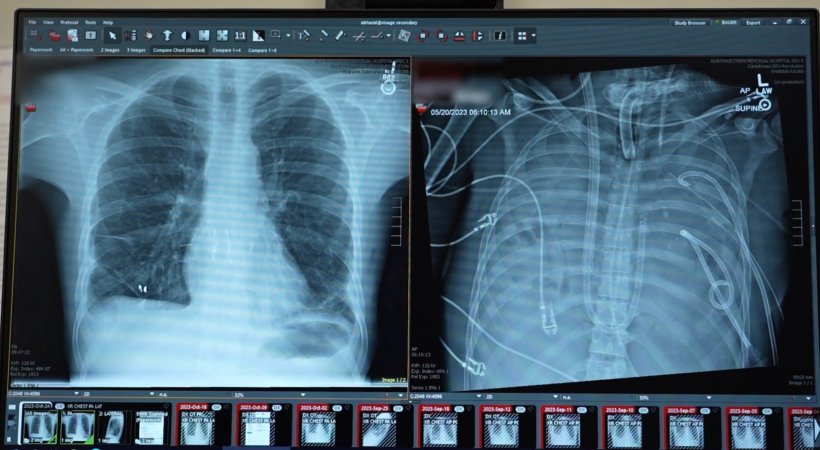

Image credit: Northwestern Medicine

Reporting in the Cell Press journal Med, surgeons describe how they removed a patient’s infected lungs and built “artificial lungs” to keep him alive until a double lung transplantation was available. The work shows how the approach may serve as a life-saving bridge to transplantation. “He was critically ill. His heart stopped as soon as he arrived. We had to perform CPR,” recalls Bharat, the lead author and a thoracic surgeon at Northwestern University. “When the infection is so severe that the lungs are melting, they’re irrecoverably damaged. That’s when patients die.”

The patient, a 33-year-old man, developed acute respiratory distress syndrome (ARDS), a life-threatening condition in which inflammation and infection overwhelm the lungs. Triggered by the flu, his lungs deteriorated rapidly and were further compromised by bacterial pneumonia. Eventually, his lungs, heart, and kidneys started to fail. A double lung transplant became his only chance of survival. The lungs were damaged beyond repair and were fueling infection. But the patient’s body was too sick to accept new lungs; it needed time to heal. “The heart and lungs are intrinsically connected,” says Bharat. “When there are no lungs, how do you keep the patient alive?”

To solve the problem, Bharat’s team engineered an artificial lung system that temporarily replaced the lungs’ functions. The system oxygenated the blood, removed carbon dioxide, and helped maintain a stable blood flow through the heart and body while the patient had no lungs at all.

Once the infected lungs were removed, the patient’s condition improved. His blood pressure stabilized, organ function recovered, and the infection subsided. Two days later, donor lungs became available, and the surgeons performed a double lung transplant. More than two years later, the patient has returned to daily life with good lung function.